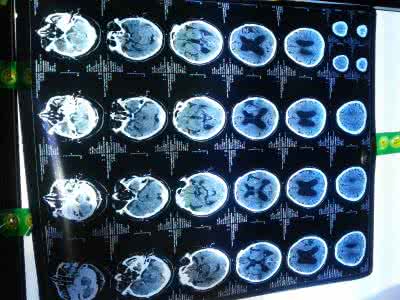

脑萎缩的中医治疗法来源:未知 脑萎缩是一种老年疾病,同时又是一种慢性疾病,目前,中医治疗脑萎缩是很多人采取的方法之一,那么,脑萎缩的中医治疗方法有哪些呢?下面就为大家具体介绍一下,希望对您有帮助。 首先,中医治疗脑萎缩的整体观

小脑萎缩表现多由遗传、脑外伤、脑梗塞、脑炎、脑缺血、缺氧、脑动脉硬化、煤气中毒、酒精中毒等引起脑实质破坏和神经细胞的萎缩、变形、消失,那么,小脑萎缩有哪些主要表现?这个问题一直以来都是大家比较关注的,以下是专家为大家